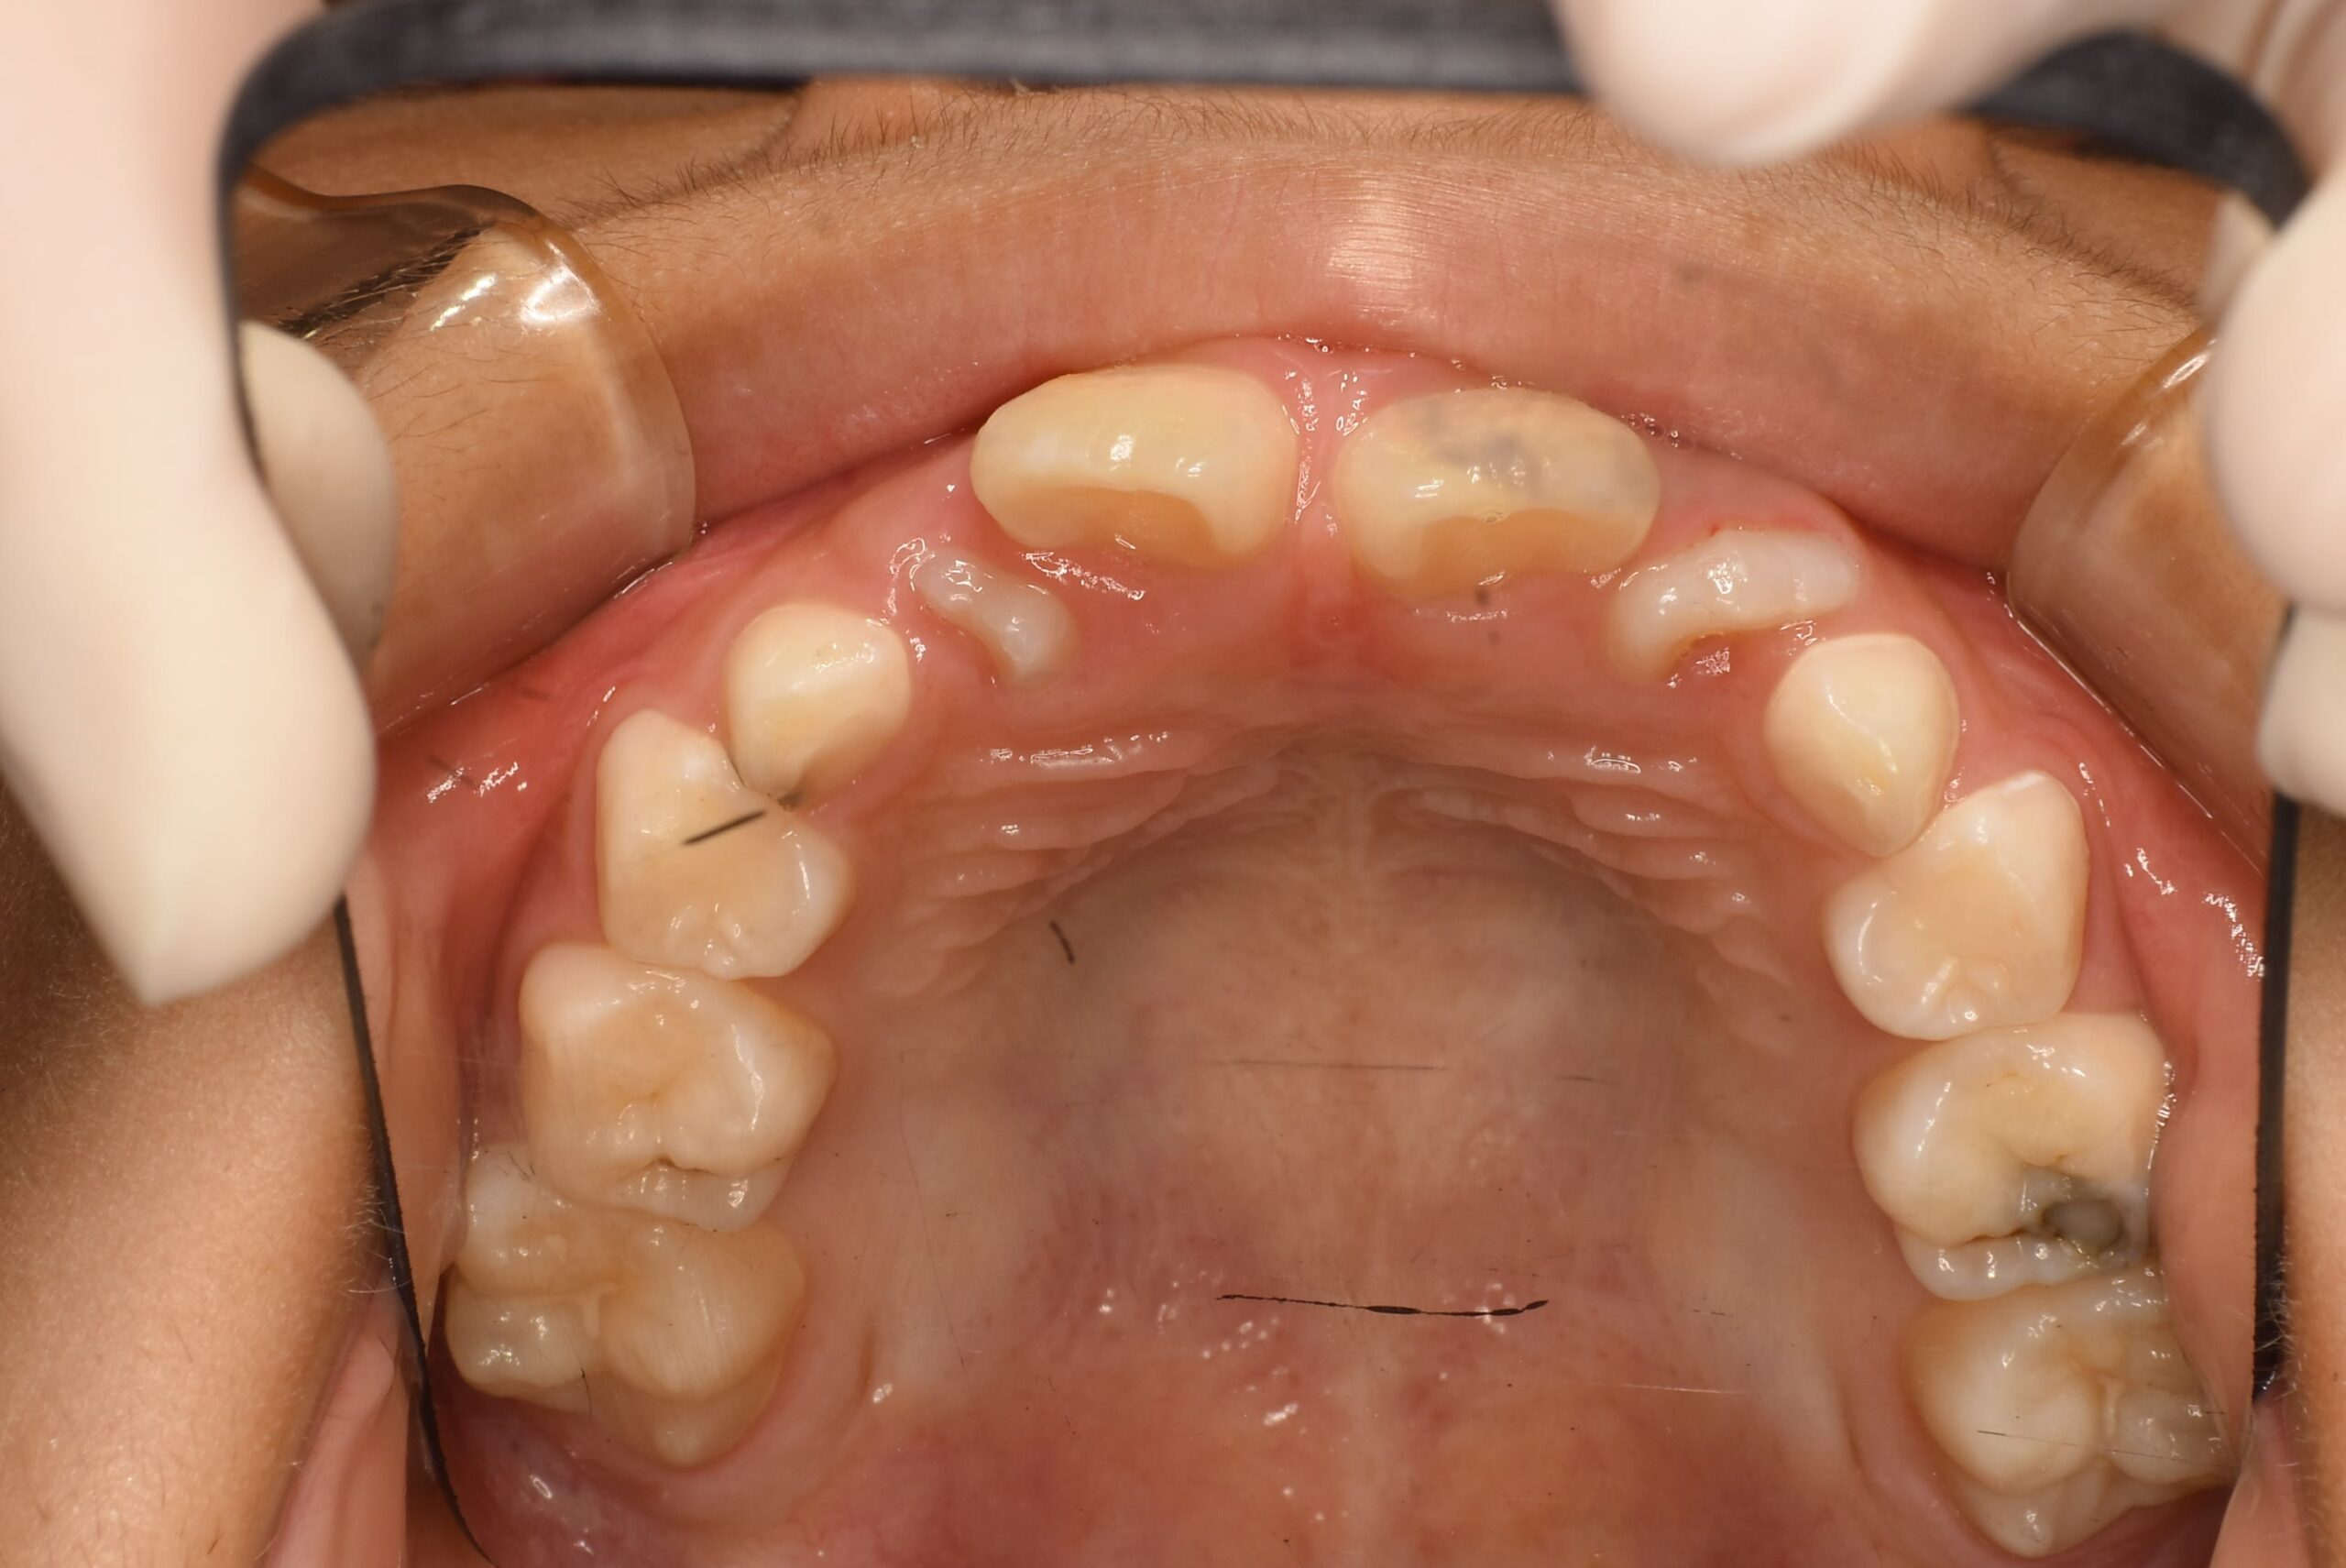

症例詳細:マイオブレースを用いた小児矯正(咬合誘導)

| 主訴 | 歯がバラバラに生えている(叢生) |

|---|---|

| 年齢・性別 | 女児・10歳(小学4年生) |

| 診断名 | 叢生(歯の生えるスペース不足)、口呼吸および舌の癖 |

| 治療内容 | 日中1時間と就寝時のマウスピース(マイオブレース)装着。あわせて呼吸・舌・飲み込み・唇を鍛えるアクティビティ(MFT)を毎日実施。 |

| 治療期間 | 2年2か月(現在も継続中) |

| 費用(税込) | 583,000円 ※検査代・装置代・月1回調整料5,500円含む |

| リスク・副作用 |

|

| 備考 | 本症例は治療途中の経過写真です。治療結果には個人差があります。 |